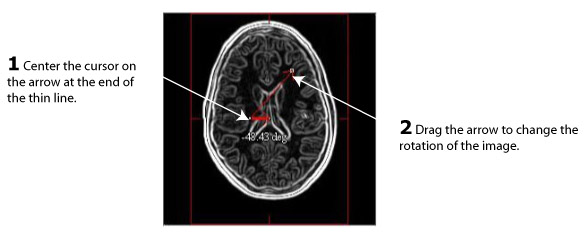

2 Move the cursor to the arrow on the thin line to the right, and align the cursor with the end of the arrow. At this time, the cursor should be a red cross.

Figure 4. Closed angle that appears on each of the images

3 Change the size of the angle by dragging the arrow on the thin line up or down depending on the type of angle you want to create. The exact number of degrees appear on the left below the angle.

4 Release the mouse button when you reach the desired number of degrees.

Figure 5. Changing the angle by dragging the arrow on the thin line